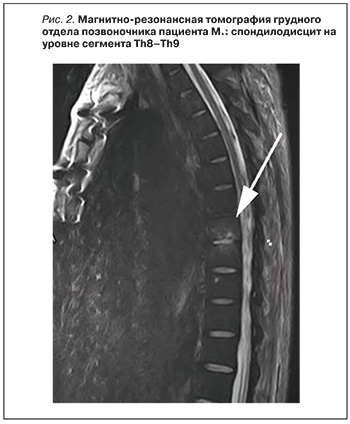

В связи с появлением жалоб на боли в спине была выполнена магнитно-резонансная томография грудного отдела позвоночника, подтверждены признаки спондилодисцита на уровне сегмента Th8–Th9 (рис. 2). Больной получил консультацию нейрохирурга: оперативное вмешательство показано не было, проводилась симптоматическая терапия.